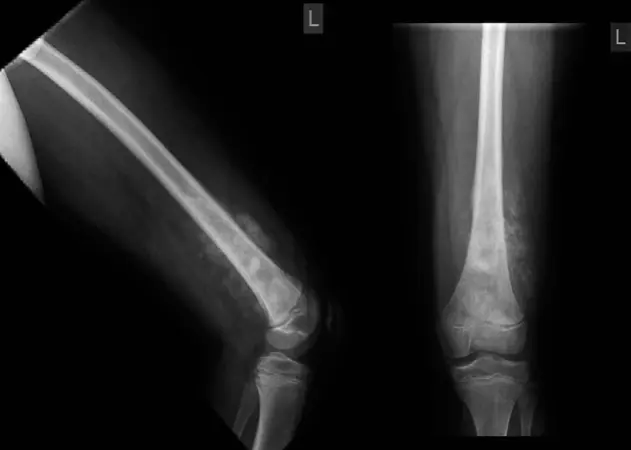

تنشأ ساركوما العظام من الخلايا العظمية الأولية (Osteoblasts) التي تتطور بشكل غير طبيعي وتتكاثر لتشكل ورمًا خبيثًا. نظرًا لأن المشاشة هي منطقة النمو النشط، فإن الخلايا فيها تنقسم بسرعة، مما يجعلها أكثر عرضة للتحولات السرطانية. هذا يفسر سبب شيوع ساركوما العظام في العظام الطويلة وحول مناطق النمو النشط مثل الركبة (عظم الفخذ السفلي والساق العلوي) والكتف (عظم العضد العلوي). إن فهم هذا الجانب التشريحي ضروري لتحديد مواقع الورم المحتملة وتوجيه عمليات التشخيص والعلاج بدقة.